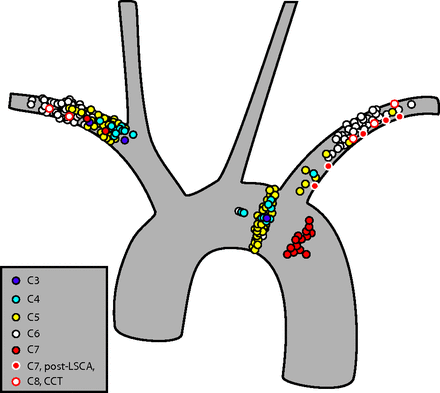

The origins of the VAs plotted against an idealized aortic arch. For this illustration, each VA origin was plotted in a 1D manner as a function of distance from the RSCA origin on the right or from the LSCA on the left. The position in any dimension other than that along the axis of the vessel is not based on anatomic data, and the distribution of vessel origins in the medial-lateral or craniocaudal dimension is used only to permit better visualization of the data points. Typical origins giving rise to VAs entering the FT at C6 are shown in white. Origins of vessels entering the FT at C3, C4, C5, and C7 are shown in purple, cyan, yellow, and red, respectively. Vessels originating along the posterior wall of the LSCA and entering at C7 are shown in red with a white outline. In addition, vessel origins entering at C7 whose vessel origin is shared with the CCT are shown in white with a red outline. Most of the high-entry vessels, which enter at C3–C5, originate in the proximal SCA on the right and directly from the arch or in the proximal subclavian artery on the left. Most of the low-entry vessels originate distal to or along the posterior wall of the LSCA in the region of the aortic isthmus.

When VA variants were mapped by their origins and coded for their level of entry to the FT, these patterns became clearer (Fig 7). While the VAs entering normally at the C6 FT originated from a relatively wide range of distances along the SCA on both sides, virtually all cases of “high-entry” at C3–C5 took origin from relatively narrow vascular segments. Overall, these high-entry vessels (entering FT at C5–C3) originated from a small segment of the RSCA, 93% originating within 2 cm of the RSCA origin. In addition, 2 cases with high-entry originated from the right common carotid artery itself. In contrast, only 14% of VAs entering the C6 FT originated within this range. On the left, these originated from the small segment between the LCCA and the LSCA, or from the proximal segment of the LSCA.

Most cases with “low-entry” at C7 originated from the aortic arch distal to the LSCA. A single right VA, originating even more distally from the thoracic aorta, entered the FT at C7 but coursed along the homologous costovertebral joint beginning at T4.

There were exceptions to the patterns we observed. For instance, in 4 cases, the LVA took origin from the aortic arch between the LCCA and LSCA and entered the FT normally at C6. In 5 cases, 2 on the right and 3 on the left, the VA took origin at a normal location on the SCA (defined here as >2 cm from the RSCA origin on the right, as described above) and entered the FT at C7. In 4 of these cases, there was a common origin of the VA and the costocervical trunk (CCT), and in the fifth case (on the left), the VA origin was within a few millimeters of the CCT.